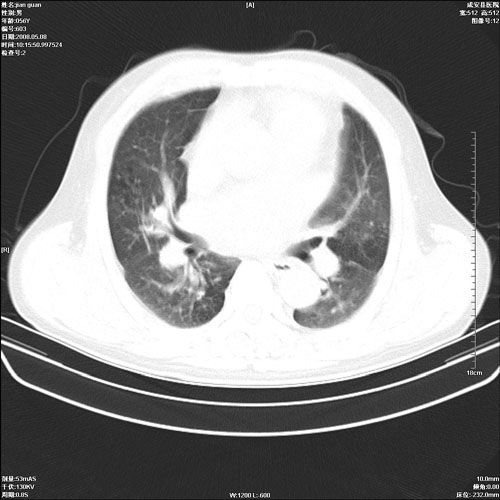

病人 男 60岁 主诉 胸闷 无明显发热 一般情况尚可。

肺结核?

两上肺陈旧性结核;慢支肺气肿、伴感染?

考虑1心功不全,肺水肿

2右上肺结核纤维性病灶、肺气肿

1.右上肺陈旧性肺结核.

2.心脏增大(以左心室增大为著),请结合b超及听诊.

1.两上肺陈旧性结核;慢支肺气肿。

2.肺门血管扩张,心脏增大,为肺心病

考虑.两上肺陈旧性结核;慢支肺气肿。肺心病

两上肺陈旧性结核,慢支肺气肿。

两上肺陈旧性结核;慢支肺气肿。肺肺间质纤维化

1.陈旧肺结核;

2.慢支肺气肿;

3.肺心病.

陈旧性肺结核,左心房扩大,左心衰竭